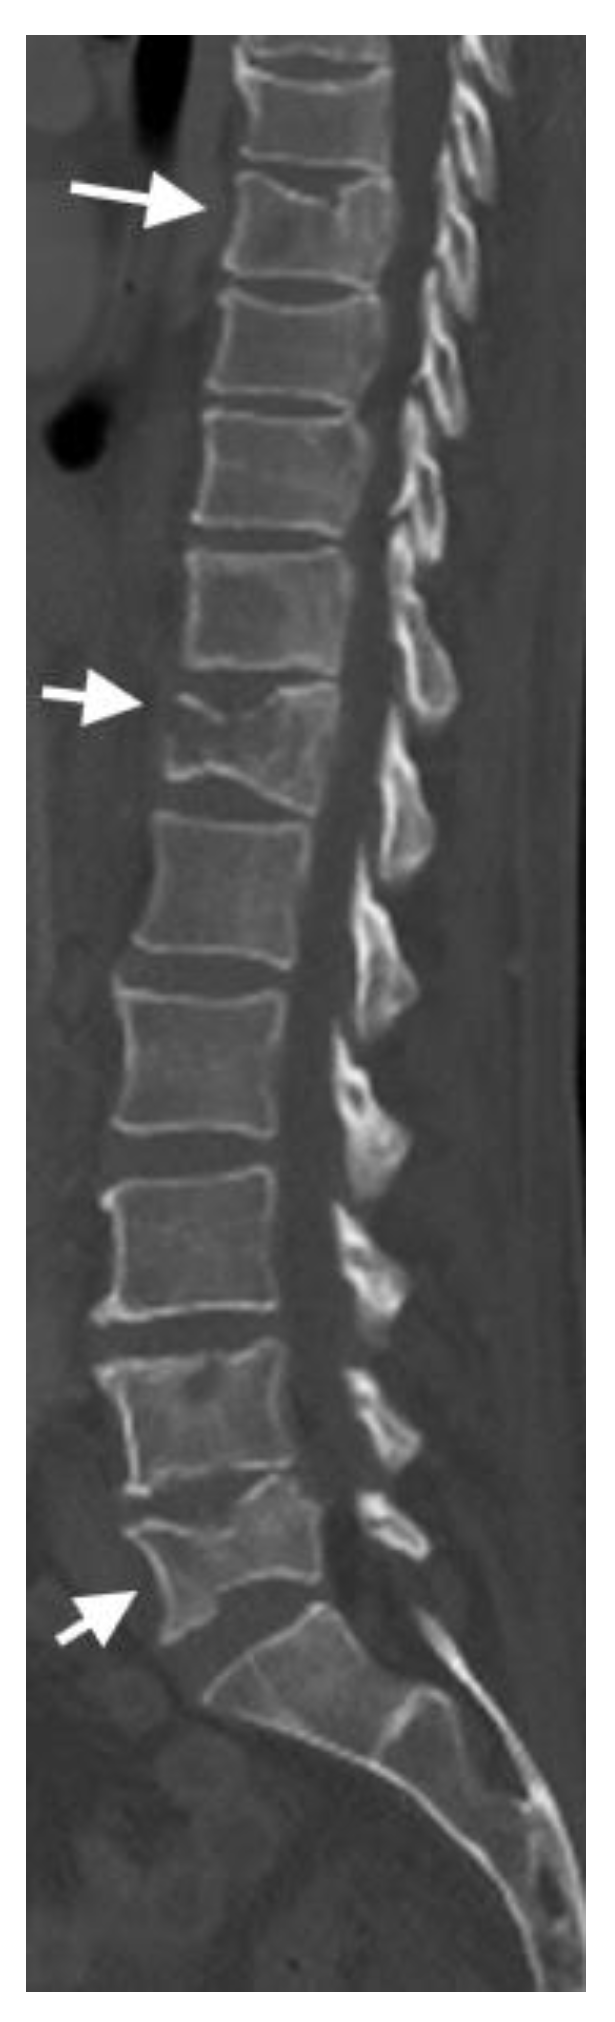

4.2. CT Scans

4.3. MRI Scans